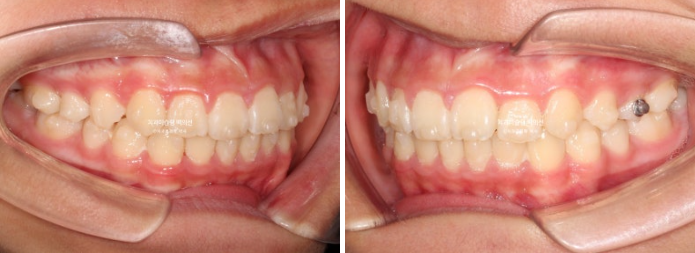

24년 1월 교정치료를 위해 온 만 10세 어린이입니다.

24.02

3년 전에 소아치과에서 앞니 부분교정을 한 적이 있다고 합니다.

그래서 위 앞니에는 중절치 두 개를 잇는 철사유지장치가 붙어있었습니다.

중심선이 약 2mm 어긋나 있고 위 앞니 치축은 한쪽으로 기울어져 있습니다.

앞니가 깊게 물리는 과개교합도 보입니다.

공간부족으로 인한 덧니가 심해 반대교합이 있습니다.